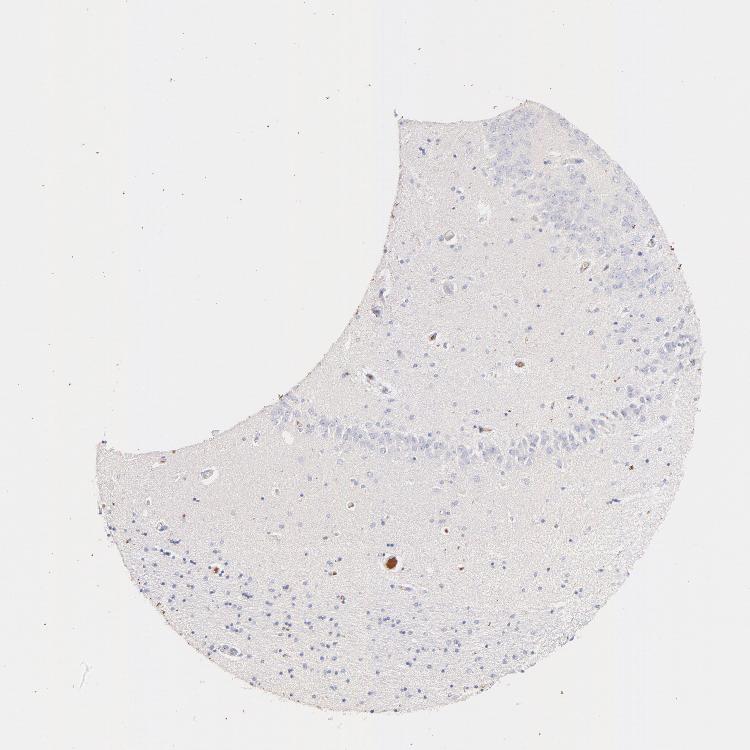

TISSUE PRIMARY DATA HIPPOCAMPUS Show tissue menu

HIPPOCAMPUS - Antibody stainingi

Antibody staining in the annotated cell types in the current human tissue is reported as not detected, low, medium, or high, based on conventional immunohistochemistry profiling in selected tissues. This score is based on the combination of the staining intensity and fraction of stained cells.

Each image is clickable and will lead to virtual microscopy that enables deeper exploration of all samples and also displays staining intensity scores, fraction scores and subcellular localization as well as patient and tissue information for each sample.

Antibody HPA003182

Glial cells Not detected

Neuronal cells Not detected